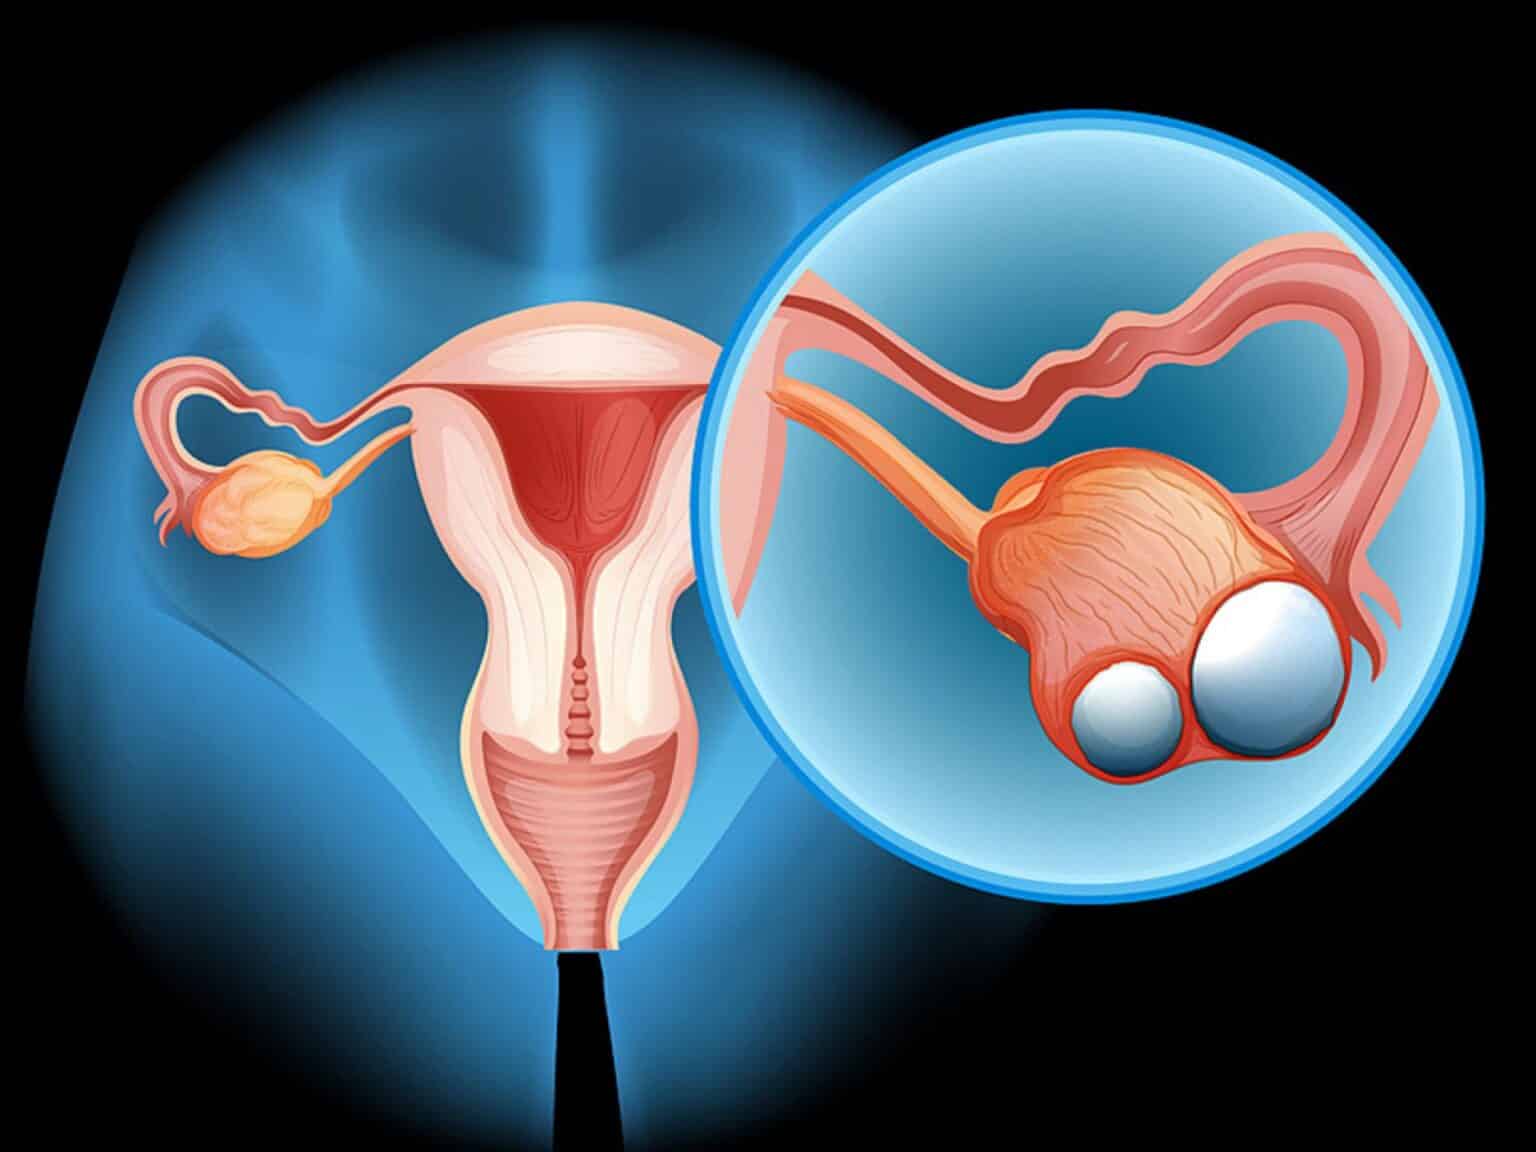

Συμπτώματα καρκίνου των ωοθηκών

Αυξημένος έλεγχος: Γυναίκες με μεταλλάξεις BRCA ή υψηλό κίνδυνο ίσως χρειαστούν μαστογραφίες και μαγνητική τομογραφία μαστού σε νεαρότερη ηλικία, καθώς και υπερήχους πυέλου (κάτω κοιλιάς) ή εξετάσεις αίματος για τις ωοθήκες.

Προληπτική χειρουργική: Ορισμένες γυναίκες επιλέγουν προληπτικές χειρουργικές επεμβάσεις, όπως μαστεκτομή (αφαίρεση μαστών) ή ωοθηκεκτομή (αφαίρεση ωοθηκών και σαλπίγγων).